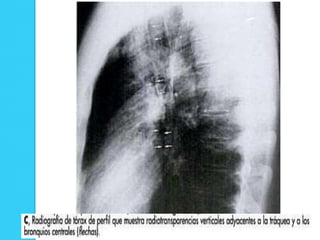

Neumomediastino

   La presencia de neumomediastino aumenta la posibilidad

de que haya un neumotórax; en estos casos se debe

buscar una línea pleural.

Neumomediastino  La presencia de neumomediastino aumenta la posibilidad de que haya un neumotórax; en estos casos se debe buscar una línea pleural.